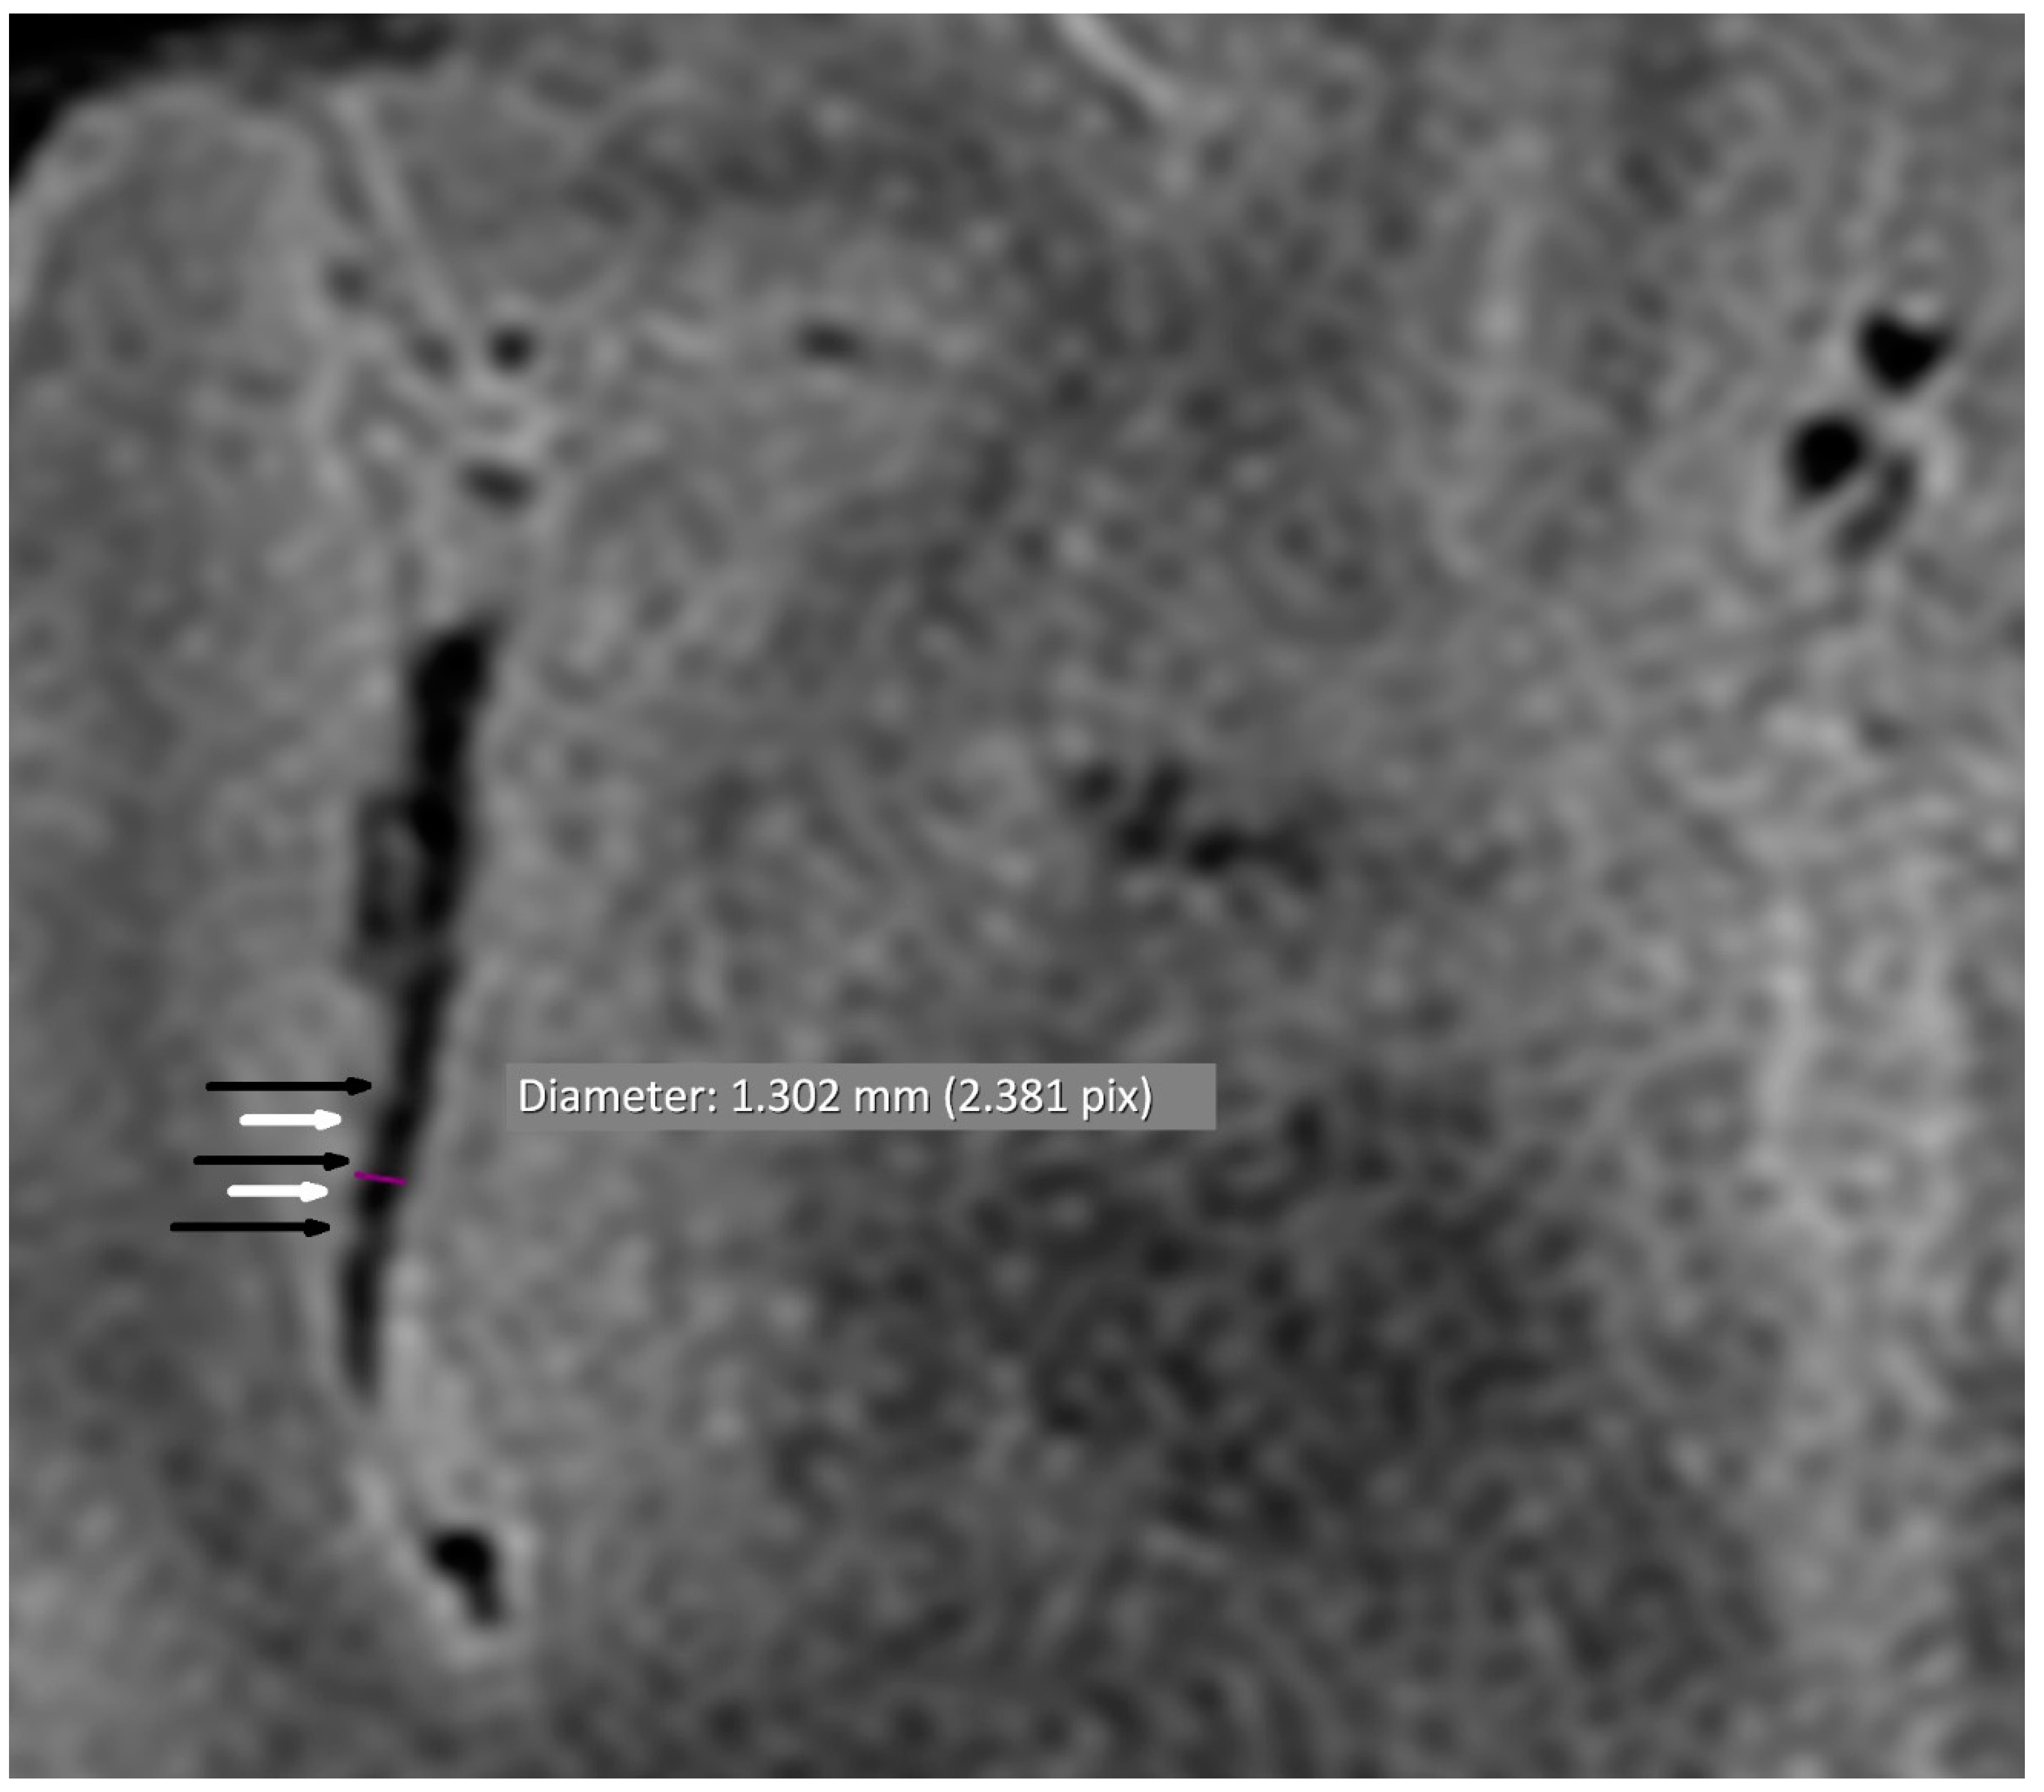

Figure 2.

Alternating narrowing and dilatation in the intracranial vessel (axial plane). BB STIR T2 axial sequence; purple—diameter; black arrow—narrowing; white arrow—widening.

Cerebral MRI in TOF scanning revealed five microaneurysms (dimensions from 1.7 × 1.8 mm to 3.5 × 4.0 mm), and two of them were localized in the right internal carotid arteria. We found only two segmental arterial narrowing in the investigated group. The occurrence of VAND was detected in 16/38 (42.1%) patients (Table 4, Figure 1 and Figure 2). Considering the different quantities of VAND, the BB MRI technique was more diagnostic than the TOF sequence (p < 0.001).